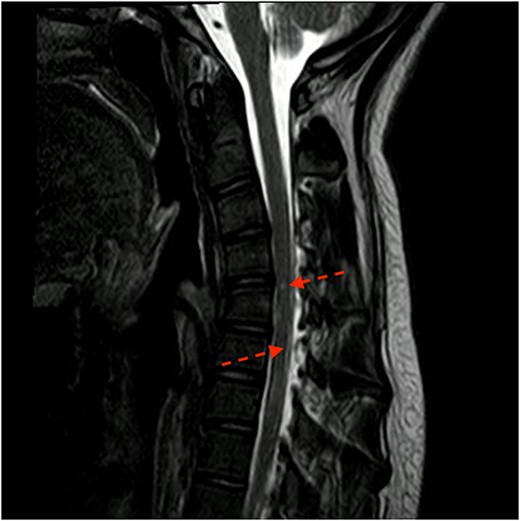

During post-operative day 1, the patient experienced paresthesias in upper and lower extremities, motor weakness (0/5 in bilateral lower extremities and 2/5 in the left upper extremity), loss of bladder sensation and urinary retention requiring a foley catheter insertion. Neurology team assessed the patient, diagnosing an anterior spinal cord syndrome. Chin stitches were removed and neck flexion was reduced to 30°, and an emergent cervico-thoracic spine magnetic resonance was performed to evaluate vascular damage. T2 and STIR sequences showed cervical kyphosis and two hyperintense lesions in the ventral spinal cord at the level of C4–C5, and the gray matter of C6–C7 (Fig. 1). Posteriorly, a brain angiogram was performed to rule out arterial occlusions with no suggestive findings of artery damage (Fig. 2).

Sagittal cut of MRI T2 sequence with evidence of medullary ischemic lesion in C5, and C6–C7 (arrows).